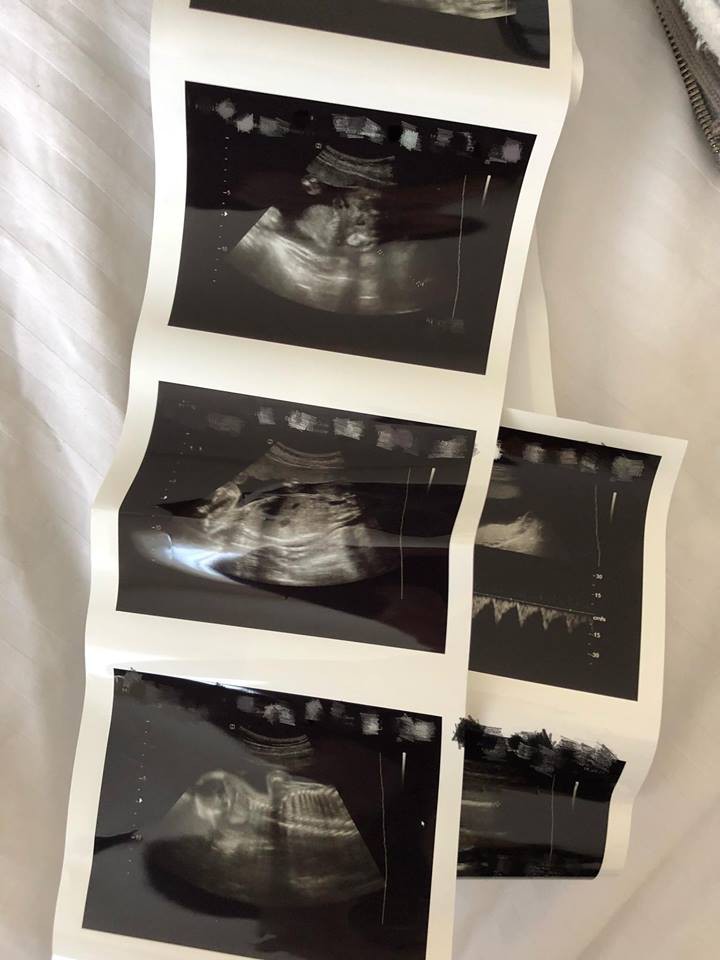

葉翠翠在IG分享超聲波照片:「今天去了婦科檢查,有好消息!胎兒比正常週數大了一點,頭仔大了12天,肚腩大了10天,大腿長了15天,醫生說陀得好好!各位準備懷孕或懷孕媽媽,真的可以參考我的分享,雖然我不能說究竟是那一個環節起了作用,但只知道我的秘方的而且確係對胎兒有幫助!今次胎兒比小王子還長大了一點,因胎小王子時是邊學邊做,但今次是一早預備好,所以兩個胎兒都有少少分別。好多人擔心胎兒過大的問題,話難生產。講真,過細係好容易,要大就唔係講一句咁簡單!現在香港一般嬰兒出生只有6磅至7磅內較為普遍,所謂的「過大」都只是8磅至8磅半,當然基因都有影響,不過想胎兒有幾健康就自己決定了。」